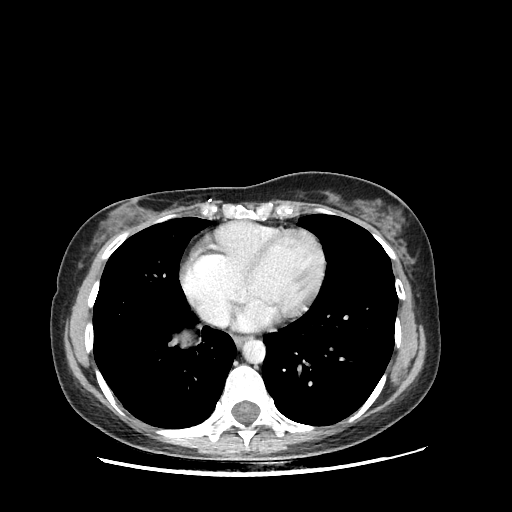

Image Grid

4Γ—3 grid: Rows show different image types (Original NATIVE, Reconstructed NATIVE, Original VENOUS, Generated VENOUS), Columns show windowing techniques (No Window, Lung Window, Mediastinum Window)

Generated VENOUS CT scan (A→B translation)

Full window (WL 1023.5, WW 4095 β†’ Low βˆ’1024, High +3071)